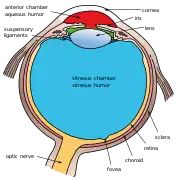

Schematic diagram of the human eye. | |

Position in the eye

The lens is located towards the front part of the vertebrate eye called the anterior segment which includes the cornea and iris positioned in front of the lens. The lens is held in place by the suspensory ligaments (Zonule of Zinn),[1] attaching the lens at its equator to the rest of the eye[2][3] through the ciliary body. Behind the lens is the jelly-like vitreous body which helps hold the lens in place. At the front of the lens is the liquid aqueous humor which bathes the lens with nutrients and other things. Land vertebrate lenses usually have an ellipsoid, biconvex shape. The front surface is less curved than the back. A human adult the lens is typically about 10mm in diameter and 4mm thick though changes shape with accommodation and size due to grow throughout a person's lifetime.[4]

Additional images

Section through the margin of the lens, showing the transition of the epithelium into the lens fibers known as the bow region. The structures of the eye labeled

The structures of the eye labeled Another view of the eye and the structures of the eye labeled

Another view of the eye and the structures of the eye labeled This svg file was configured so that the rays, diaphragm and crystalline lens are easily modified[69]